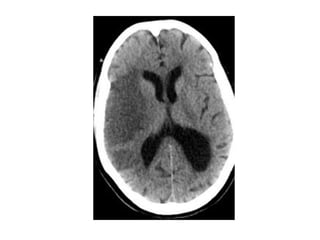

A patient with an occlusion of the right internal carotid artery , the hypoperfusion in

the right hemisphere resulted in multiple internal border zone infarctions, this

pattern of deep watershed infarction is quite common and should urge you to

examine the carotids